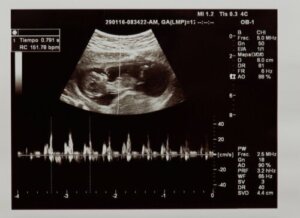

Sykkeellä tarkoitetaan sitä, kuinka monta kertaa sydän supistuu minuutin aikana. Sikiön sydämensyke on havaittavissa raskauden ensimmäisinä viikkoina ultraäänellä tai Doppler-monitorilla.

Ensin lääkäri arvioi, onko sikiöllä kuultavissa sykettä, ja tarkistaa näin sikiön elinvoiman. Lisäksi hän arvioi, kuinka monta kertaa sydän lyö minuutissa. Normaaleina pidetyt arvot sikiövaiheessa ovat 120–160 lyöntiä minuutissa.

Vauvan sydämen anatomiaa ja fysiologiaa voidaan arvioida jo kohdussa. Tämän mahdollistavat raskausajan ultraäänet, joilla voidaan arvioida muun muassa sikiön sydämen terveyttä ja sykettä.

Toisen raskauskolmanneksen aikana voidaan määrätä morfologiseen ultraääneen, jossa vauvan elimiä tutkitaan perusteellisesti. Siinä tarkastellaan huolellisesti sikiön sydämen rakenteita, kuten kammioita, läppiä ja verisuonia.

Tällaisella ultraäänellä arvioidaan myös mahdollisia ongelmia sydämen mekaanisessa toiminnassa tai sähköimpulssien johtumisessa. Morfologisella ultraäänellä voidaan diagnosoida myös synnynnäiset sydänsairaudet, jotka voivat aiheuttaa vauvalle ongelmia syntymän jälkeen.